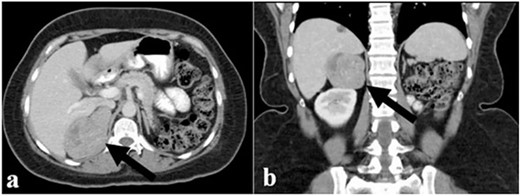

The endocrinological study showed a hypersecretion of cortisol with suppressed ACTH (550 mcg/l, ACTH 1.1 ng/ml, urinary free cortisol 255 mcg/24 h, positive overnight Nugent test). The serum concentration of renin and aldosterone and the urinary concentration of metanephrine are instead normal. Therefore, the patient underwent an abdominal CT scan that showed a right adrenal lesion of about 7 cm with an adenomatous appearance (Fig. 1). The saggital 3D reconstruction of CT scan in venous phase had raised the suspicion of short course of the adrenal vein in the lower lateral lip of the mass (Fig. 2). To better define the relationship between the neoplasm and the inferior vena cava, the vascularization of the adrenal gland with any anatomical anomalies and the specific location of the middle adrenal vein, a 3D printed model was created in 1:1 size based on the preoperative CT scan.

Sagittal 3D reconstruction of CT scan in venous phase. In particular, the images had raised the suspicion of the short course of the adrenal vein in the lower lateral lip of the mass.